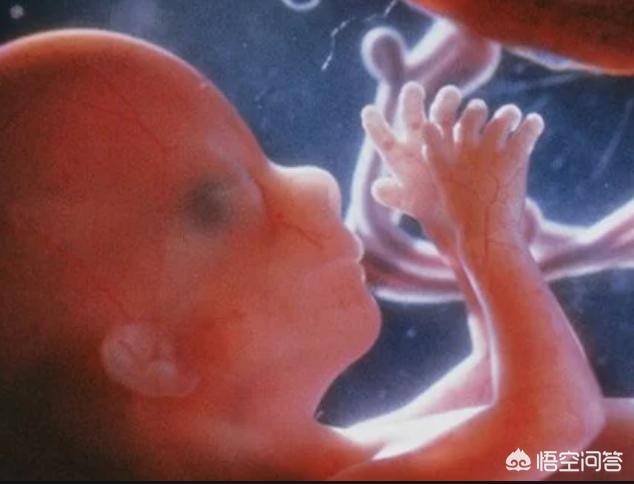

简单看看宝宝在肚子里面的眼睛发育过程

怀孕6-7周:宝宝眼睛开始发育了

怀孕10周:宝宝的眼皮开始出现了

怀孕11周:宝宝的眼皮完全发育好了 , 可以闭眼了

怀孕28周左右:宝宝可以睁眼、闭眼并且四处转动眼睛了 。 我们可以想象这就是宝宝在妈妈肚子里面“练习”转眼睛呢 。